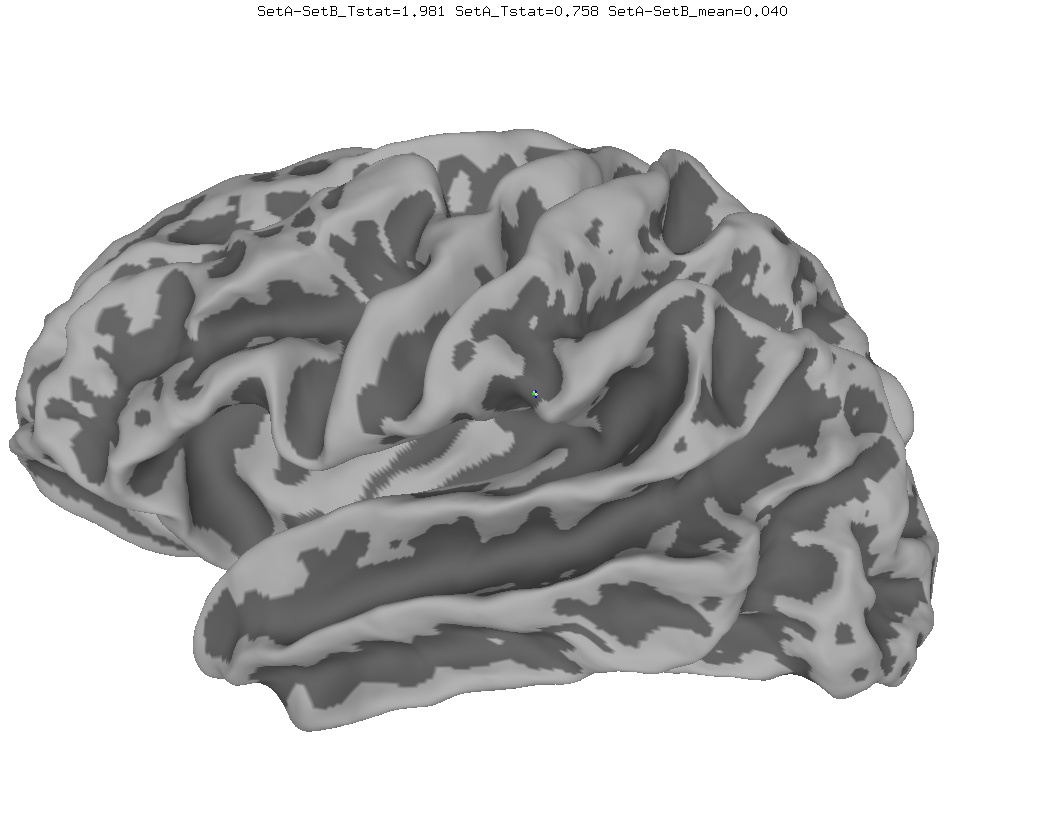

Anatomical Data

New

Old

In March 2017, the AFNI team discovered a bug in the MapIcosahedron program. Here is a comparison of group average results with the old and new (fixed) versions. If you have old surface averages and would like to fix them, you can use a script like this to create new surfaces, then re-run your surface averaging processing stream.